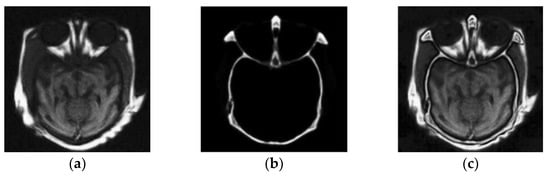

3.2. Field of Medical Imaging